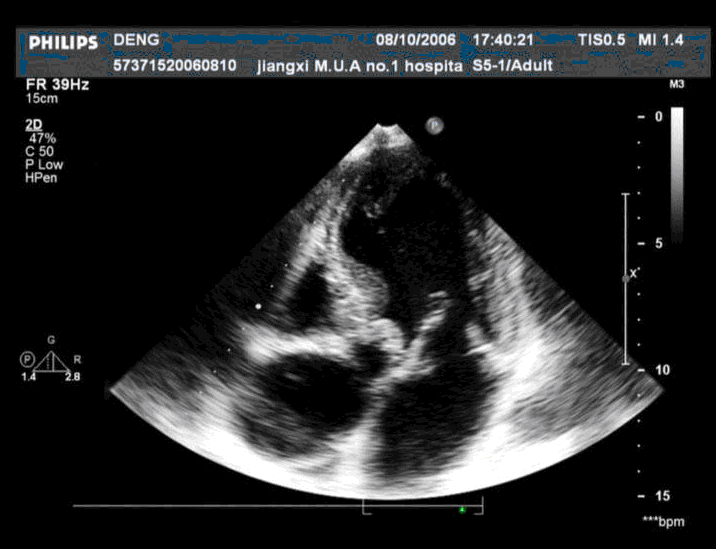

患者,男,50岁,发热半月余,全身不适,乏力,食欲缺乏。根据超声心动图,最可能的诊断是 CF20160315_19.gif CF20160315_20.gif CF20160315_21.gif CF20160315_22.gif

• B.感染性心内膜炎